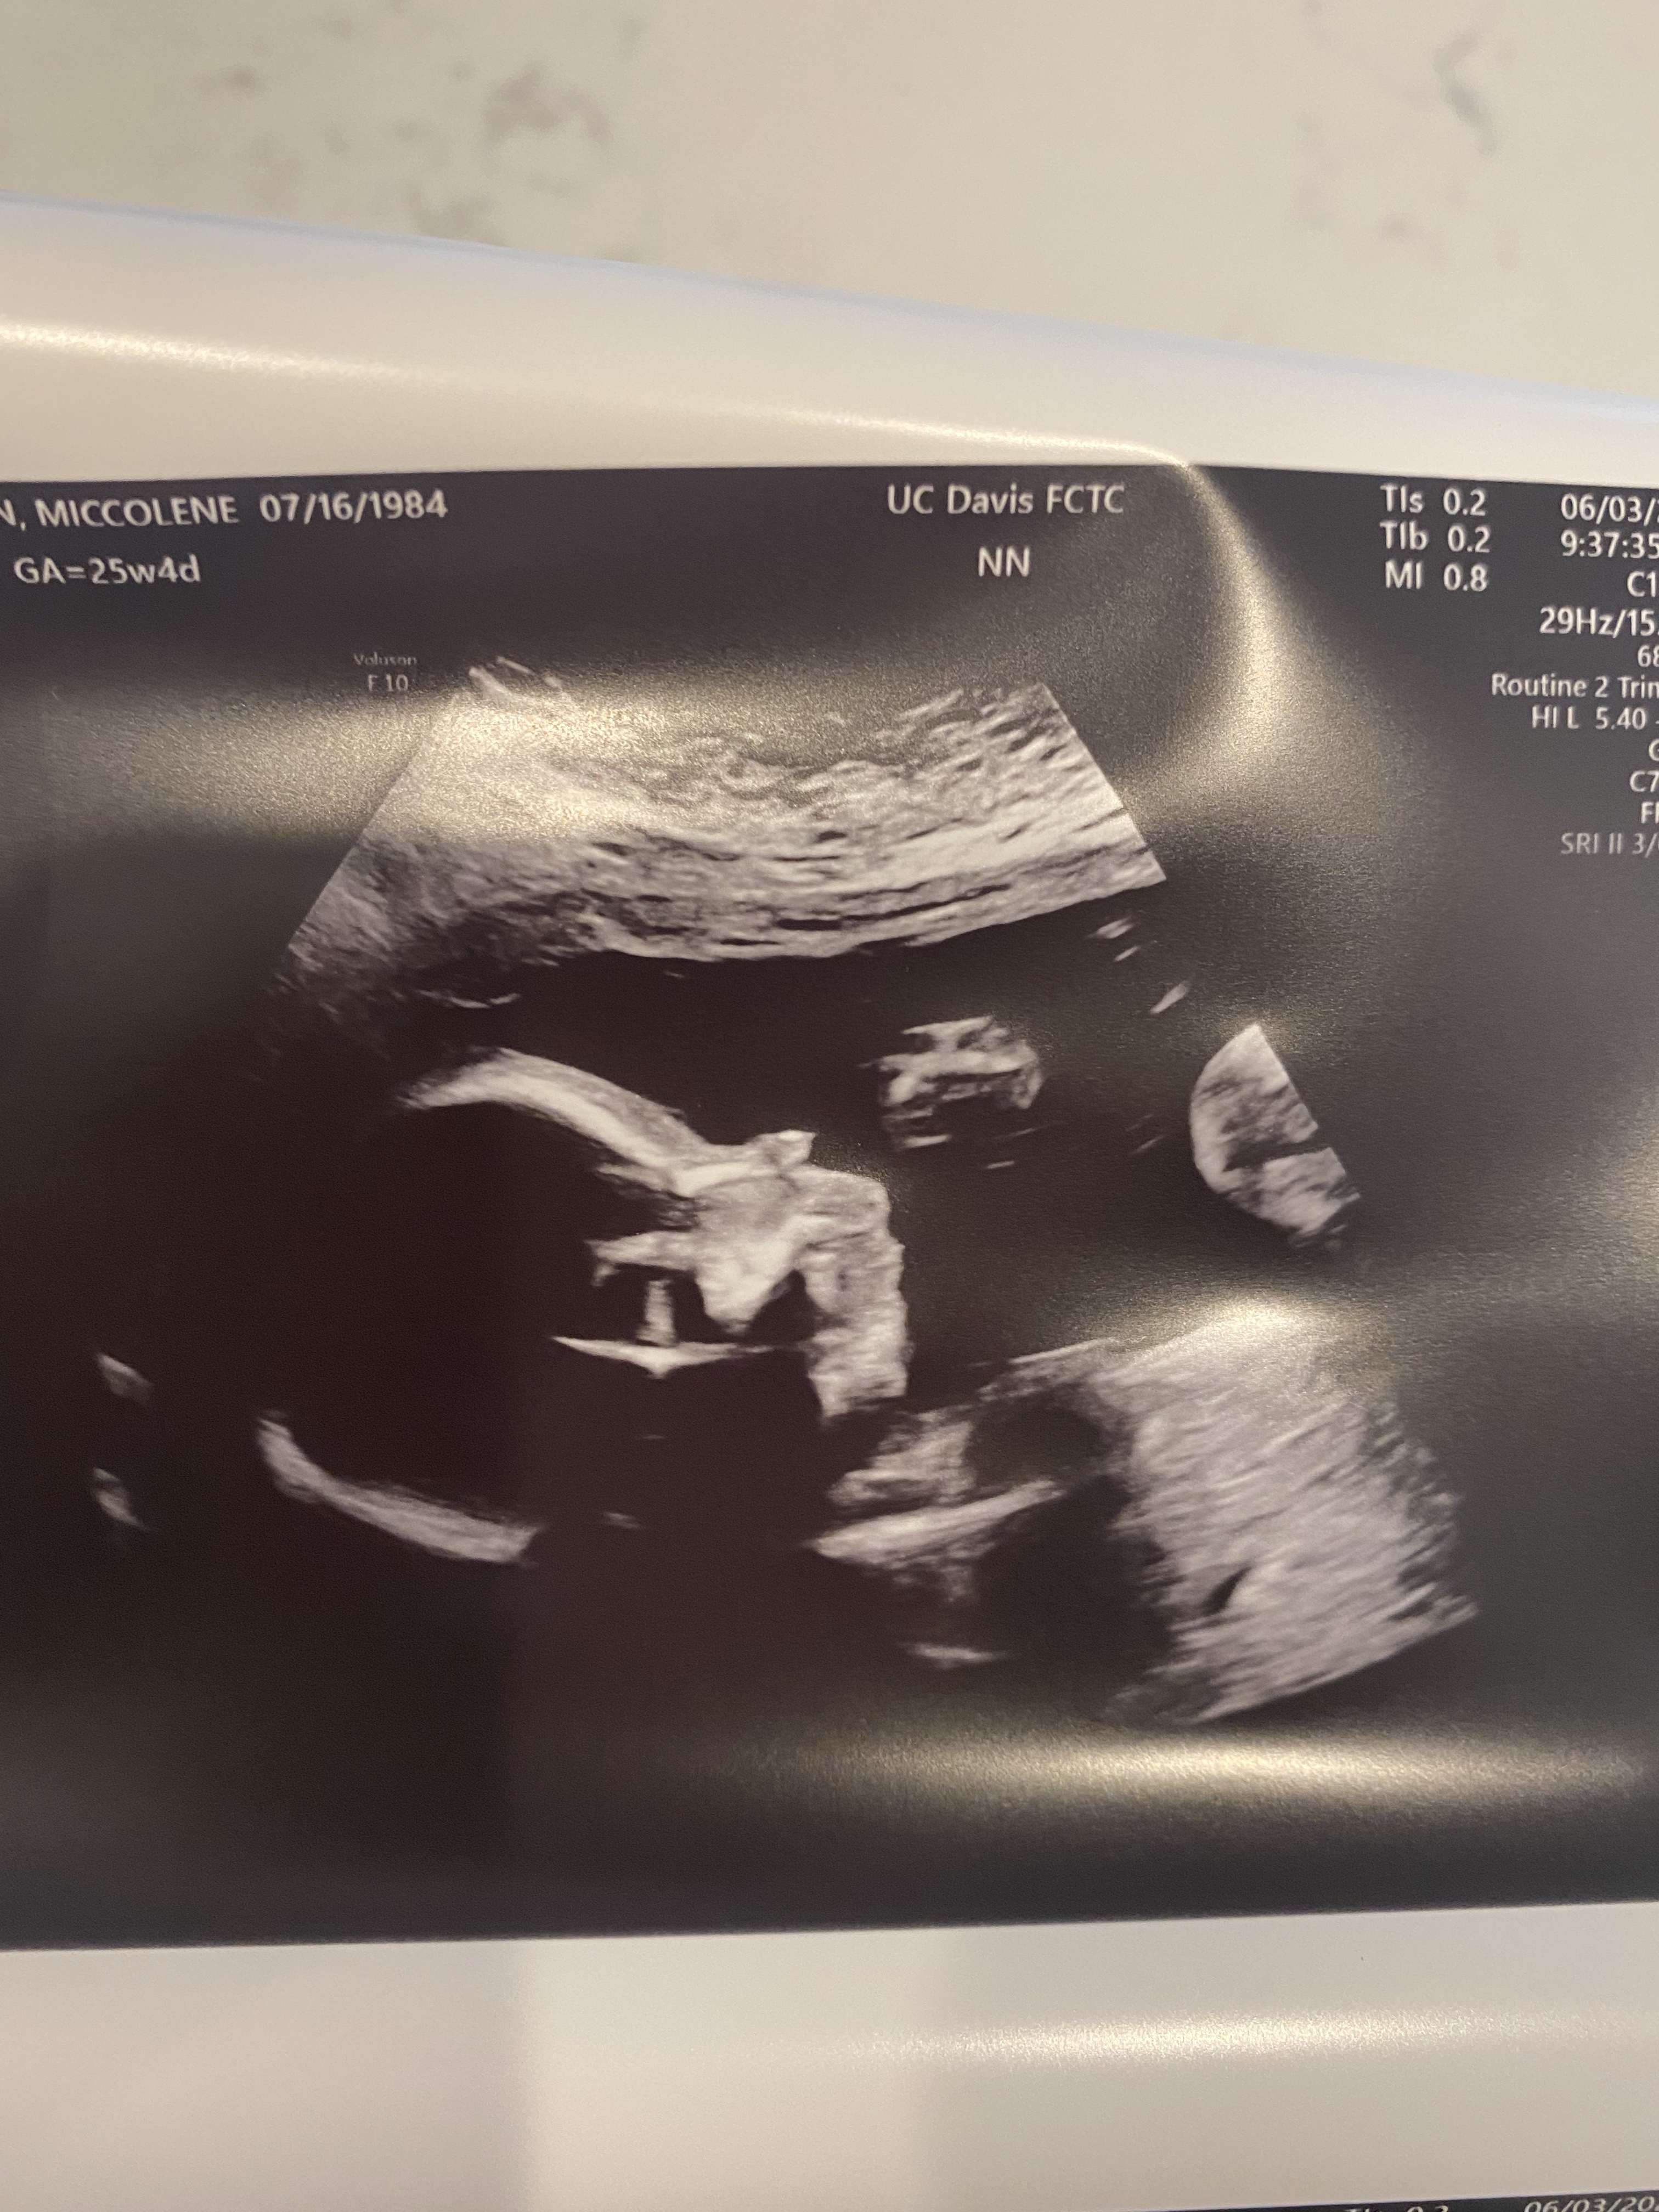

The first week of June we drove down to UC Davis for our fetal echo and anatomy scan. We waited a long time for this appointment, I think I was something like 26 weeks along when we finally got it down. I was thrilled to confirm that she is indeed a lady baby and soooo relieved that her anatomy scan looked perfect. I was so nervous to talk to the pediatric cardiologist, but he said she looks great. So much relief. She was measuring right on track, perfectly healthy.